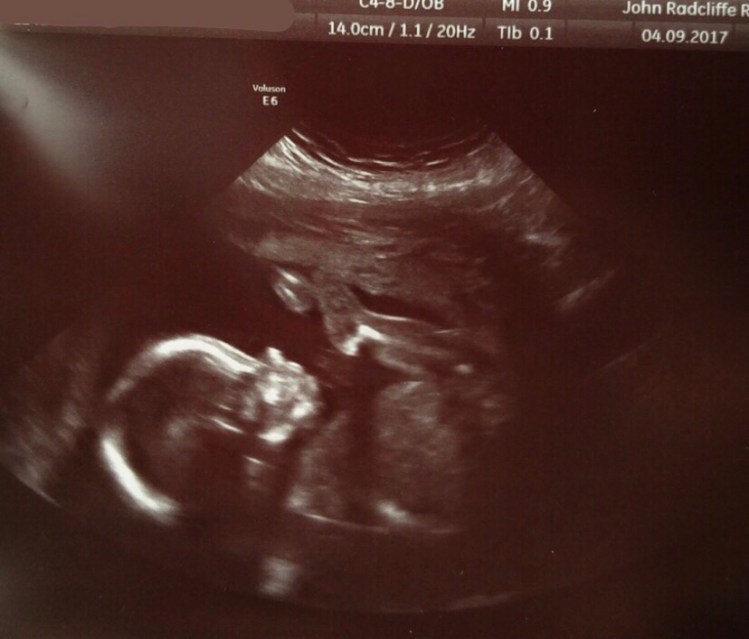

Clara at our 20 week scan:

This time last year we were caught up in the excitement of pregnancy. We knew tomorrow, 4th September 2017, was extra exciting because we would see our little baby again at the 20 week scan. It coincided with my brother’s birthday so it was perfect – we thought.

Precisely a year ago tomorrow, we found out Clara’s stomach was on the wrong side.